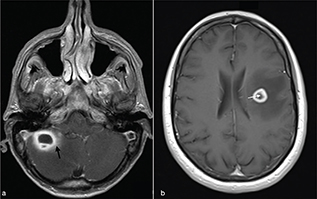

These include high-grade gliomas (WHO grade IV) and metastases. They usually exhibit a T2w hypointense, irregular or incomplete, capsular rim.8 After injection of Gd, gliomas show non-homogeneous enhancement with some nodular areas (Figure 13). Metastases, on the other hand, can exhibit an enhancement pattern similar to pyogenic abscesses. However cystic neoplasms, often have a thicker medial margin if compared with pyogenic BA (Figure 6).9 Peripheral dark signals on SWI can be also found in glioblastomas and are related to the neoplastic intralesional neoangiogenesis and haemorrhage.8 As a rule, necrotic brain tumours have high ADC values. However low ADC values have been described in hyper-cellular tumour such as metastases from lung, breast, colorectal and testicular cancer (Figure 11).5 Moreover, necrotic tumours usually show an increase of neoangiogenesis with higher values of rCBV than abscesses in the periphery of the lesion.

FIG 13. Necrotic Tumour in a 38-Year-Old Man: (a-c) a Left Temporal Lobe Cystic Mass is Shown. On T1w+Gd (c), the lesion shows irregular rim-enhancement. The central part of the lesion shows increased diffusivity (d, e) consistent with intratumoural necrotic degeneration. The rCBV map (f) showed increased perfusion within the enhancing rim of the lesion (open arrow). Final diagnosis was glioblastoma.